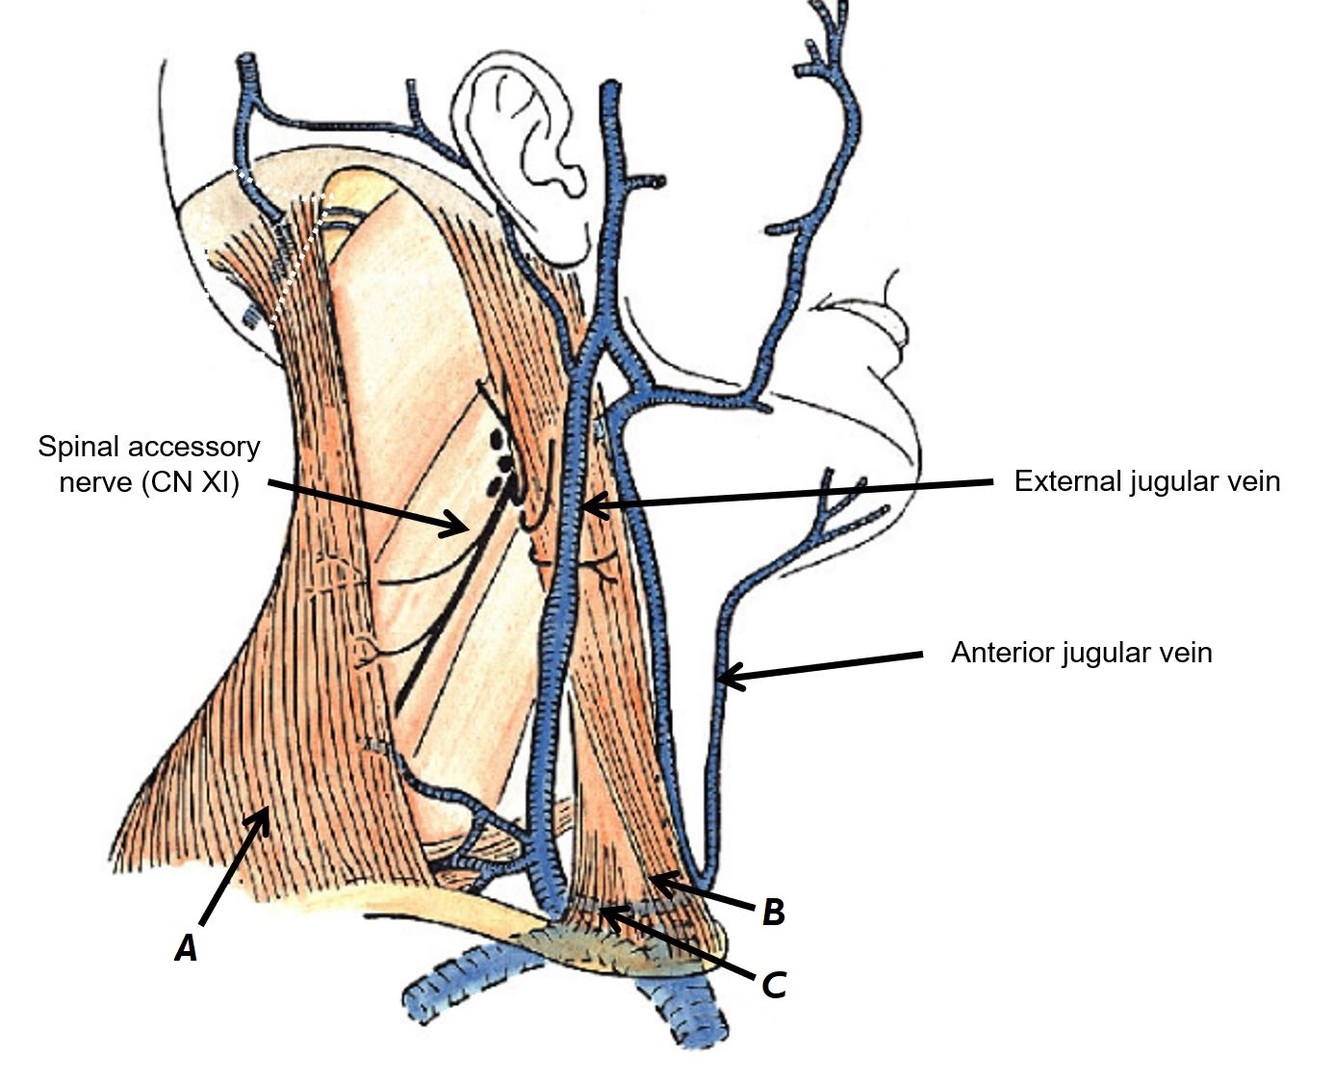

Name structures A, B and C

A - Spinal accessory nerve (CN XI)

B - External jugular vein

C - Anterior jugular vein